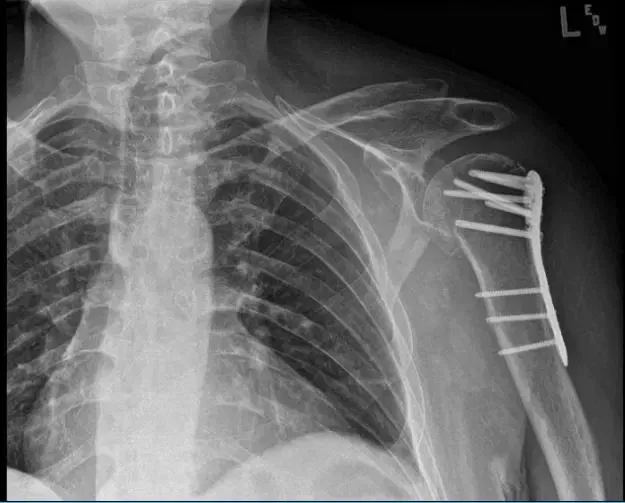

Patient seen today having complaints with his left shoulder. He stated that he fell off a ladder. And his left shoulder is the most affected one. He brings his X-ray with him. X-ray noted a comminuted fracture of the humeral head and neck and no change in position of fracture fragments compared to the left shoulder.

X-ray of the left shoulder